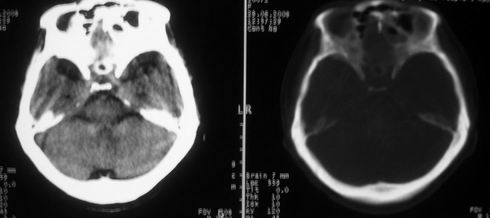

女,55岁,右侧颌下肿物3年。

右侧胸锁乳突肌后方软组织密度肿块,界限清楚。多考虑:血管源性肿瘤!

鼻咽左侧壁增厚,呈结节样突入鼻咽腔内,左侧咽隐窝消失,须考虑鼻咽癌可能,建议鼻咽纤维镜检查以明确诊断。